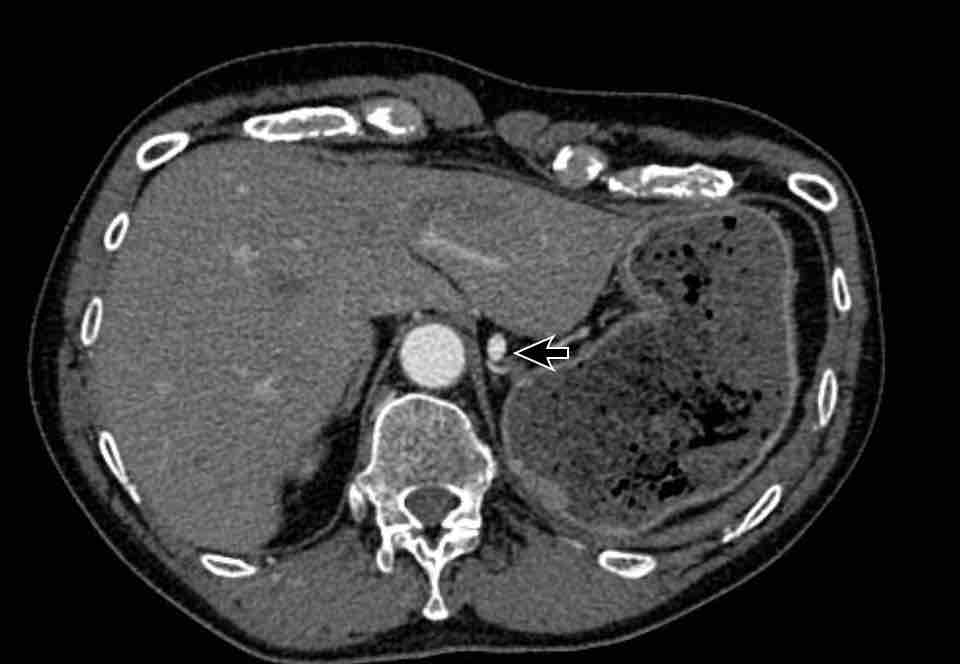

Hình ảnh

PAPVR bên trái phát hiện tình cờ với dẫn lưu trên tim của máu từ thùy trên trái vào tĩnh mạch tay đầu trái (các mũi tên).